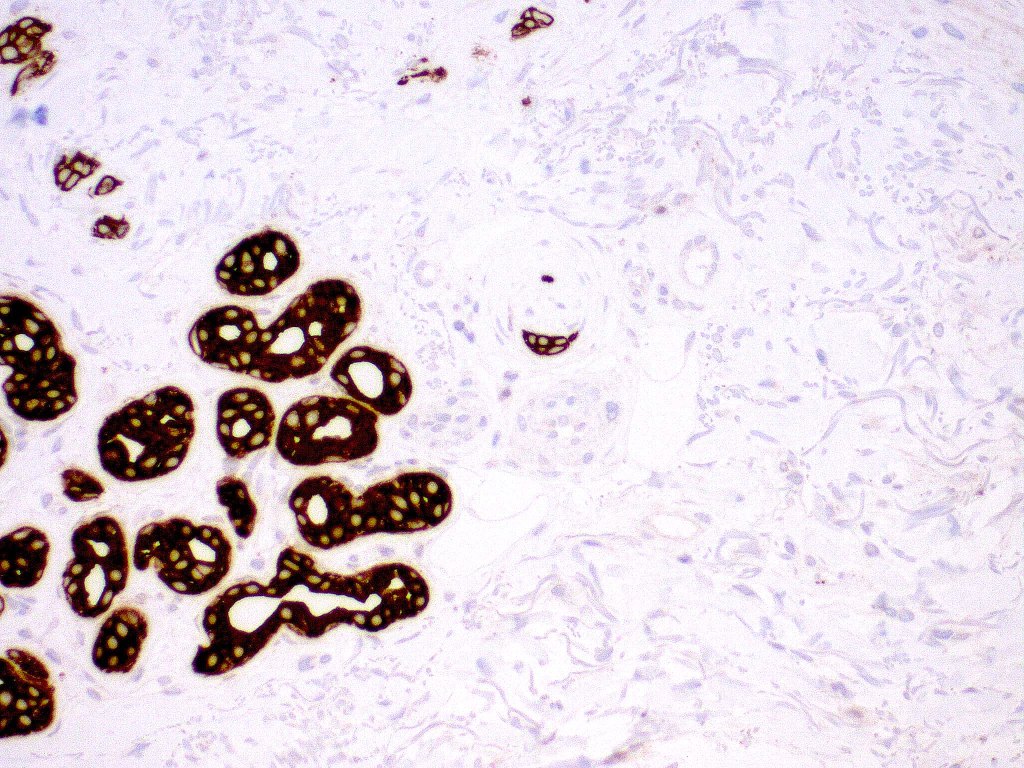

•CK20 highlights Merkel cells

. EMA & CEA show no evidence of ductal differentiation